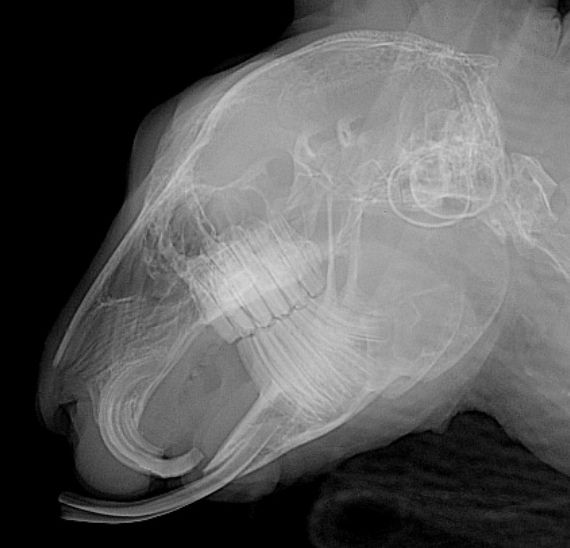

Les dents des lapins et des rongeurs herbivores poussent en continue. Par conséquent, elles continuent à croitre toute la vie de l'animal. Parfois, ces dents sont mal alignées et peuvent empêcher plus ou moins sévèrement la mastication, ce qui se traduit par de l'anorexie (refus de manger) chez un lapin ou un cobaye. Cette maladie dentaire est appelée malocclusion dentaire. La malocclusion dentaire est particulièrement fréquente chez les lapins, cobayes et chinchillas. Elle est liée en priorité à un défaut d'usure des dents (manque de foin) et généralement à une surconsommation de granulés. Par ailleurs, des facteurs génétiques et/ou des carences en vitamines (notamment en vitamine C chez le cobaye) sont également mis en cause.

Pour prévenir cette maladie, seule la consommation de foin (foin de Crau ou de phléoles) ou d'herbe fraîche permet l'usure efficace des molaires. Les signes de malocclusion sont des signes de salivation, de refus de s'alimenter, de l'amaigrissement et l'apparition de sécrétions oculaires. En cas d'infection, on observera l'apparition d'abcès dentaires. Le traitement fait appel à la taille des dents sous anesthésie (appelée parage dentaire) par un vétérinaire spécialisé. Cette taille de dent est, si possible, réalisée à l'aide d'une caméra endoscopique pour examiner les dents localisées dans le fond de la cavité buccale et évaluer des lésions plus discrètes.

Abcès dentaires

Les abcès dentaires chez le lapin sont généralement secondaires à une malocclusion dentaire. Cette malocclusion entraine la formation de crevasses ou de pointes dentaires, formant dans un deuxième temps une surinfection puis un abcès. Dans certains cas, les abcès peuvent se former en arrière de l'oeil et faire ressortir l'oeil de son orbite. Le traitement de l'abcès passe d'abord par une évaluation précise des tissus infectés et de l'origine de l'infection (racine dentaire, corps étranger,...). Si cet étape n'est pas réalisée, les risques de récidives sont presque inévitables.

Pour déterminer l'origine et les caractéristiques de l'abcès, l'idéal est de réaliser un examen d'imagerie précis comme le scanner. Le scanner correspond à un examen radiographique en trois dimensions. Le traitement de choix est typiquement chirurgical et médical. Certaines de ces chirurgies peuvent être particulièrement complexes et nécessiter l'utilisation d'un endoscope.